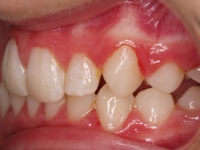

El paciente A.J. de 11 años, acude a nuestra consulta con apiñamiento maxilar importante. El canino lateral (12) está en mordida cruzada. Presenta una Clase II molar y canina, y la línea media está desviada. Se realizó un tratamiento con brackets autoligables metálicos de smartclip 022. La duración del tratamiento fue de 22 meses.

El paciente actualmente ha terminado el tratamiento con brackets y lleva una contención fija de 2-2 en maxilar y 3-3 en mandibular; para complementar también lleva una férula ESSIX durante la noche.